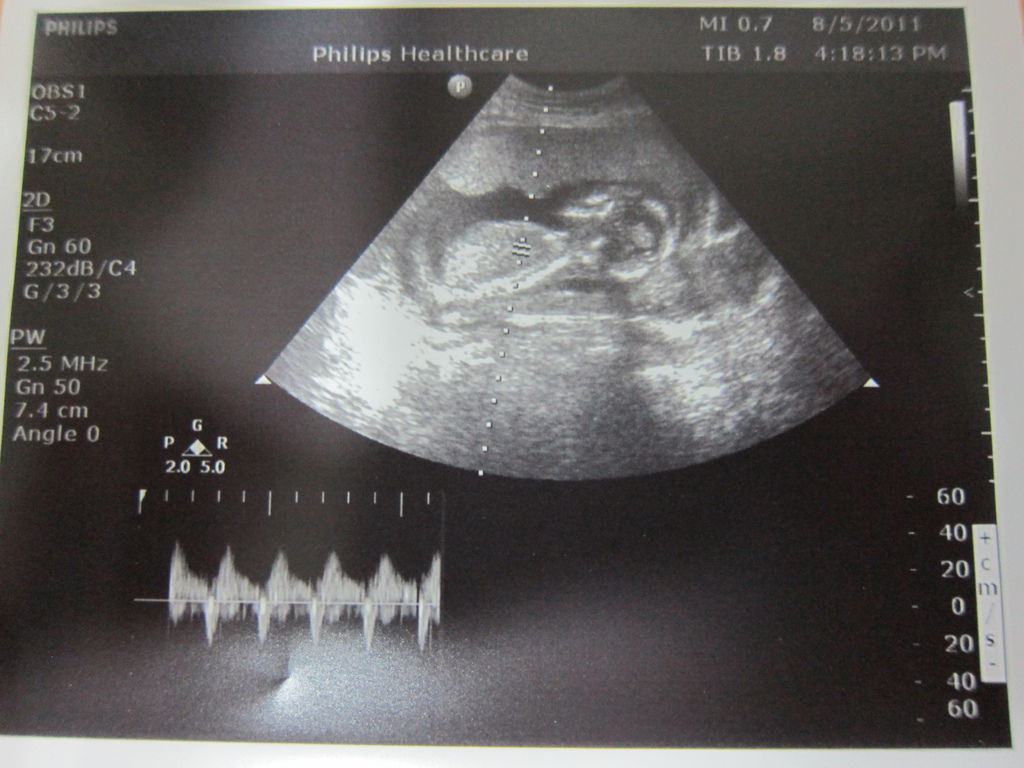

是的!!!我有二寶了!!